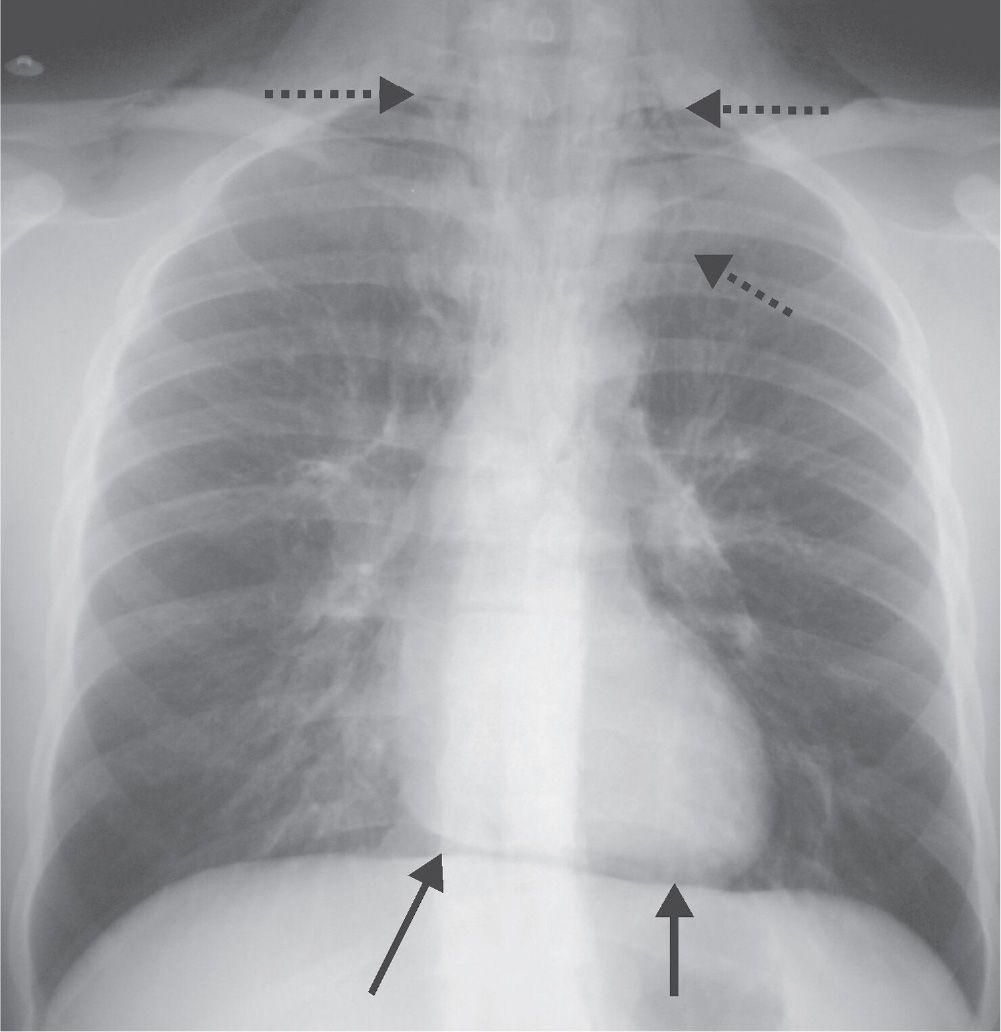

Figure1. Chest radiograph (posteroanterior view) showing hyperlucent What Is Lung Field Lucency Lucent area in the lung can be caused by pockets of air called bulla and blebs. Areas of diminished lung density are frequently identified both on routine chest radiographs and chest ct examinations. These pockets of air have no discernible wall and can. Abnormal lucency of the lung can be unilateral or bilateral, focal or diffuse. Areas of diminished lung. What Is Lung Field Lucency.